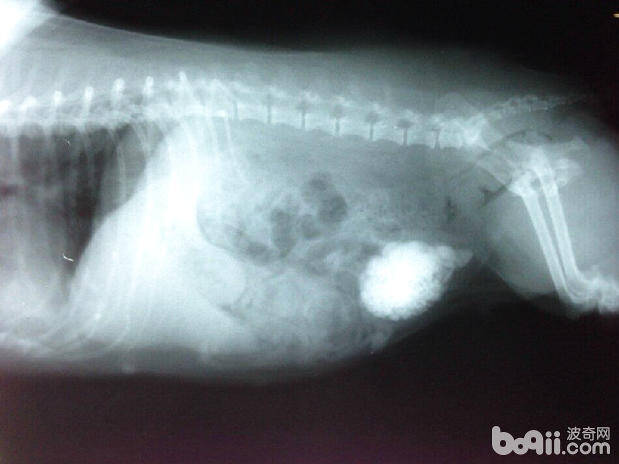

• 犬尿道结石的诊断

犬尿道结石的诊断

犬尿结石是犬的一种常见病。犬尿结石包括肾脏结石、输尿管结石、膀胱结石和尿道结石。膀胱和尿道结石最常见的两种结石,相对而言肾脏和输尿管结石则较为少见。犬尿结石主要见于中老年犬,公犬常常发生膀胱和尿道同时